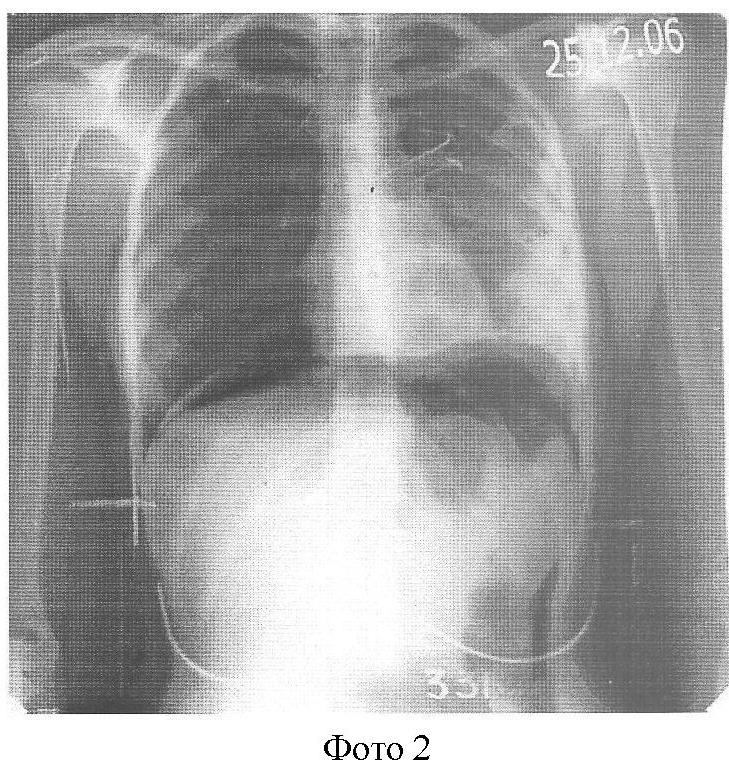

На фоне противотуберкулезного антибактериального лечения в амбулаторных условиях наложен искусственный пневмоперитонеум, обзорная R-грамма от 20.12.06 г. (Фото 2), где мы наблюдаем приподнятый воздухом купол диафрагмы, который поддерживался в течение 15 мес. За это время жидкость полностью рассосалась без выраженных спаек. Обзорная R-грамма от 30.01.07 г. (Фото 3).